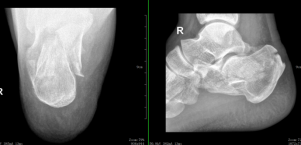

术前照片